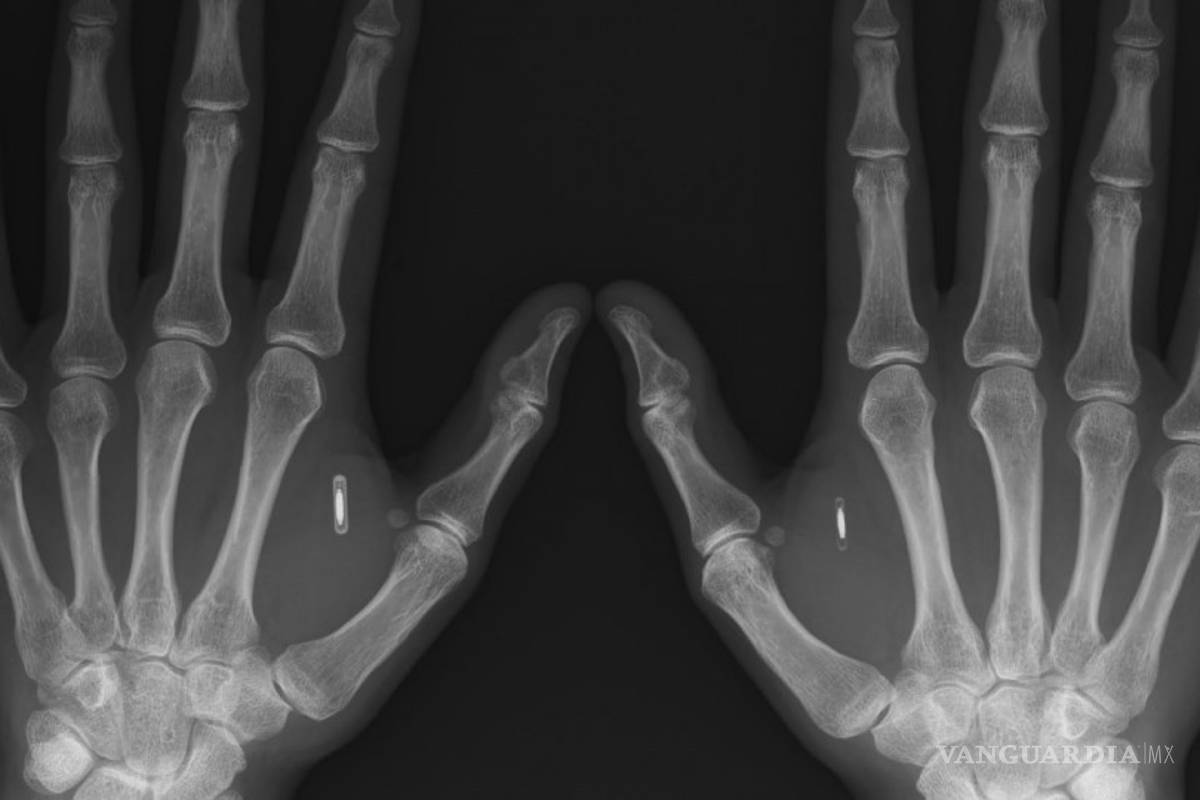

Casi cualquier parte de tu cuerpo puede usarse como forma de identificación. La disciplina que se encarga de medir un rasgo tuyo para darte entrada a ciertos datos se llama biometría.

Las principales formas implementadas o estudiadas incluyen reconocimiento de huellas dactilares, rostro, iris, voz y geometría de la mano.

Muchas otras modalidades se encuentran en distintas etapas de desarrollo y evaluación como el DNA, las orejas, la forma de escribir o caminar, las venas e incluso el olor.